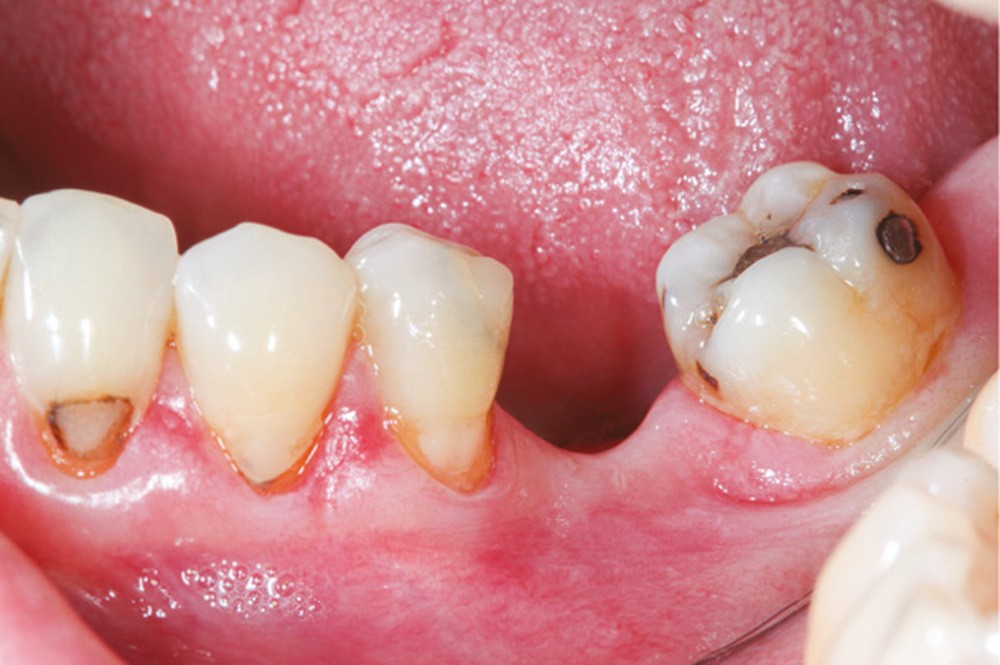

Cette version, quand elle se produit, modifie les espaces interdentaires et complique l’hygiène proximale des patients. Des caries peuvent alors se développer en interproximal sans que cela soit forcément visible à l’examen visuel (fig. 3 et 4). Les radios de type bite-wing (rétro-coronaires) prennent alors tout leur sens (fig. 5 et 6).

La version des dents distales peut aussi avoir des conséquences parodontales désastreuses : sur un parodonte réduit, une hypermobilité peut se développer, une poche parodontale peut aussi apparaître. Chez un patient parodontal, un « effet domino » est possible, des extractions non compensées diminueront donc le pronostic des dents restantes (fig. 7 à 9).